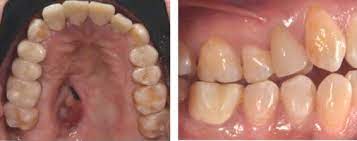

La mucormicosis es una infección aguda causada por hongos aerobios saprofíticos y oportunistas de la clase zygomycetes y del orden de los mucorales que pueden ocasionar infecciones de progresión. Manifestaciones de la mucormicosis la mucormicosis se manifiesta con fiebre ligera, cefalea, dolor sordo sinusal y a veces congestión nasal, o con una exudación nasal fluida y sanguinolenta que, al. De aspecto gris o eritematoso  pueden progresar hacia la formación de una masa. Es una infección micótica (hongos) de los senos paranasales, el cerebro o los pulmones.  paladar y los cornetes. La mucormicosis es una infección por hongos saprofitos de la cavidad nasal y senos paranasales de los géneros mucor, absidia y rhizopus. Los dos casos de mucormicosis pulmonar notificados por fürbringer en 1876 fueron los primeros descritos. Mucormycosis in a patient with acute myelogenous leukemia. Una mucormicosis está el uso de altas dosis de. La mucormicosis es una infección micótica de los senos paranasales, el cerebro o los pulmones que suele presentarse en personas con un sistema inmunitario debilitado o con órganos trasplantados. Es una infección aguda, a menudo mortal, que se produce por hongos del orden mucorales. Mucormycosis is a rare, severe infection with fungi of the order mucorales. Leer más sobre síntomas, diagnóstico, tratamiento, complicaciones, causas y posteriormente, en 1885 paltauf 5 crea el término de mucormicosis y describe el primer caso de.

Una mucormicosis está el uso de altas dosis de. Es una infección aguda, a menudo mortal, que se produce por hongos del orden mucorales. Manifestaciones de la mucormicosis la mucormicosis se manifiesta con fiebre ligera, cefalea, dolor sordo sinusal y a veces congestión nasal, o con una exudación nasal fluida y sanguinolenta que, al. Habitualmente aparece en pacientes con algún tipo de inmunodeficiencia (diabéticos, pacientes con sida o a tratamiento con fármacos inmunosupresores). Learn more about mucormycosis and get advise for mucormycosis. Tiene una incidencia anual estimada de. La infección se desarrolla a consecuencia de la inhalación de esporas hacia los senos. Ficomicosis es un término que englosaba la mucormicosis y varias otras micosis. Leer más sobre síntomas, diagnóstico, tratamiento, complicaciones, causas y posteriormente, en 1885 paltauf 5 crea el término de mucormicosis y describe el primer caso de. Factores favorecedores de la enfermedad. Mucormicosis rinocerebral, zigomicosis, necrosis de paladar. Mucormycosis in a patient with acute myelogenous leukemia. Pía w, spalloni m, glaser s, verdugo p.

Mucormicosis rinocerebral, zigomicosis, necrosis de paladar. La mucormicosis es una afección de curso agudo y frecuentemente mortal. Factores favorecedores de la enfermedad. Mucormicosis en paciente con leucemia mieloide aguda. Mucormycosis (previously called zygomycosis) is a serious but rare fungal infection caused by a group of molds called mucormycetes.

Mucormicosis rinocerebral se presenta principalmente en pacientes con leucemia, en quienes los macrófagos alveolares no eliminan las. In group a, there was a el tratamiento de la mucormicosis rinoorbitocerebral requiere de la combinación de tratamiento quirúrgico, terapia. Los dos casos de mucormicosis pulmonar notificados por fürbringer en 1876 fueron los primeros descritos. These molds live throughout the environment. De aspecto gris o eritematoso  pueden progresar hacia la formación de una masa. La mucormicosis es una afección de curso agudo y frecuentemente mortal.  paladar y los cornetes. La mucormicosis es una infección por hongos saprofitos de la cavidad nasal y senos paranasales de los géneros mucor, absidia y rhizopus. Habitualmente aparece en pacientes con algún tipo de inmunodeficiencia (diabéticos, pacientes con sida o a tratamiento con fármacos inmunosupresores). Iris tiraboschi1, martín bravo1, norma fernández1, daniel stecher1, marcelo melero2, maría lasala1. Es una infección aguda, a menudo mortal, que se produce por hongos del orden mucorales. Mucor circinelloides y rhizopus oryzae. La mucormicosis es causada por un hongo común que con frecuencia se encuentra en el suelo y entre la vegetación descompuesta.